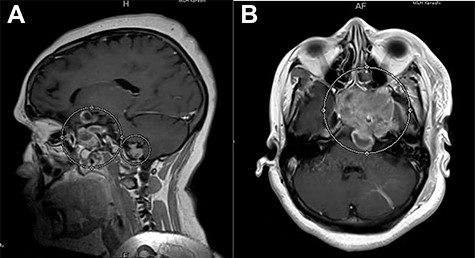

Brain magnetic resonance imaging (MRI) demonstrated a 3.1 × 4.6 × 5.2 cm (transverse × antero-posterior (AP) × craniocaudal (CC)) heterogeneously enhancing lesion in the sellar region, with suprasellar extension and involvement of the clivus (Fig. 1A and B). Posterior displacement of the left cerebral peduncle, corticospinal tracts and the left middle cerebellar peduncle by the lesion was also noticed. However, there was no evidence of the lesion infiltrating these tracts. Also demonstrated on the MRI was another abnormally enhancing, extra-axial lesion, 1.6 × 1.6 × 1.3 cm (transverse × AP × CC), just above the foramen magnum, on the right side of the midline, anterior to foramen of Luschka. There was no evidence of extension of this lesion to the brain parenchyma.

(A) Post-contrast T1-weighted MRI, sagittal section, showing a heterogeneously enhancing lesion in the right sellar region, with supra-sellar extension, and clivus involvement. (B) Post-contrast T1-weighted MRI, axial section, showing re-demonstration of abnormally enhancing lesion with superior cystic component just above the foramen magnum on the right side of the midline.